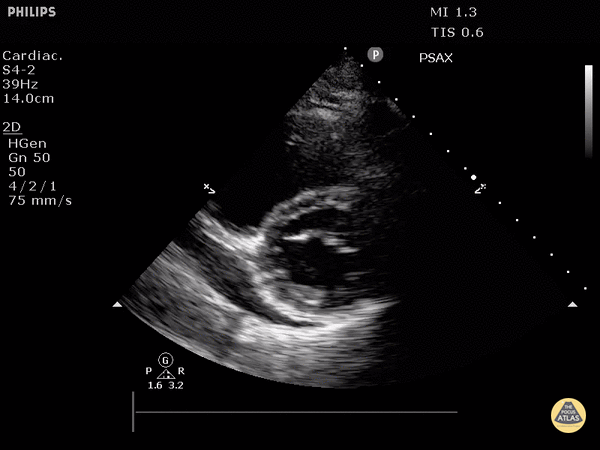

Pericardial Disease - Cardiac Tamponade (Parasternal Short-Axis View)

Parasternal short axis view demonstrating evidence of diastolic RV free wall collapse. Justin Bowra MBBS, FACEM, CCPU Emergency Physician, RNSH et al. (Dr. Orr)